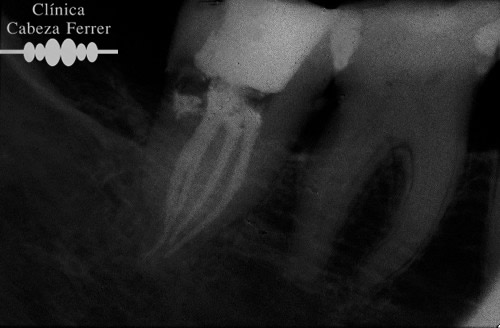

En primer lugar se explora la pieza y se realiza un estudio radiológico. Si es necesario se pone anestesia local y se aísla en diente para mantenerlo limpio y seco durante el tratamiento. A continuación con el instrumental adecuado se realiza un orificio en la corona del diente y a través de él, mediante unos pequeños instrumentos llamados LIMAS, se extrae la pulpa. Posteriormente la cámara pulpar y los conductos radiculares se limpian, se esterilizan, se rellenan y se sellan herméticamente. Con un control radiológico se comprueba que el tratamiento se ha realizado correctamente. Ahora es el momento de reconstruir la anatomía del diente y si es necesario recubrirle con una corona para evitar su posterior fractura. En la mayoría de los casos, la endodoncia se realiza en una sola sesión.

La endodoncia rotatoria avanzada es una novedosa técnica de instrumentación mecanizada que se realiza con un tipo de limas especiales de níquel-titanio. El auge del níquel-titanio surgió en la década de los sesenta, al ser utilizado por la NASA, principalmente en la fabricación de antenas de naves y satélites espaciales. Es este material, el que impulsa el desarrollo de los sistemas rotatorios en endodoncia. Estos instrumentos tienen la característica de de ser muy flexibles, por lo que pueden trabajar dentro de los conductos radiculares impulsados por un motor de baja velocidad, ejecutando una rotación de 360º hasta en los conductos curvos. De esta manera se combina la instrumentación manual convencional con la mecanizada consiguiendo así un resultado final con alta precisión, mejor limpieza, irrigación y terminación de los conductos, menos fracasos y unas restauraciones más duraderas.